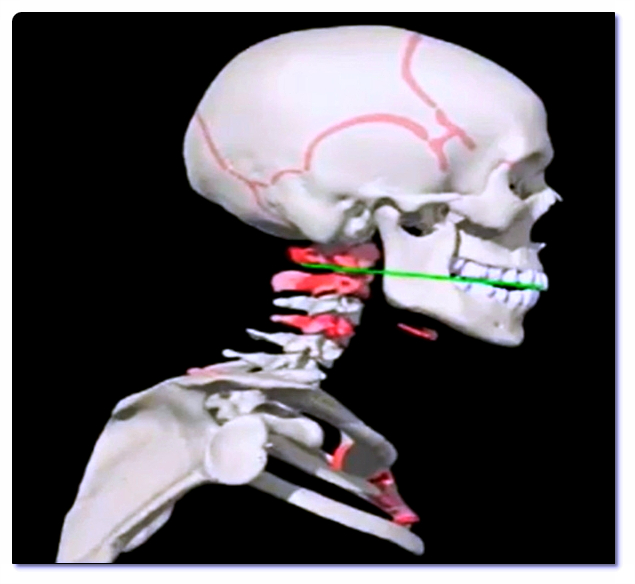

턱관절은 머리뼈와 아래턱뼈가 맞물려 움직이는 복잡한 구조입니다.

관절 내부에는 관절원판(디스크)이라는 조직이 있어 충격을 완화하는 역할을 합니다.

그런데 이 디스크가 제자리를 벗어나면 ‘딱’ 하는 소리가 나는데, 이를 정복성 관절원판 전방변위라고 부릅니다.

턱관절은 머리와 척추를 이어주는 중요한 축입니다.

턱 정렬이 틀어지면 목, 어깨, 척추까지 영향을 미치게 됩니다.